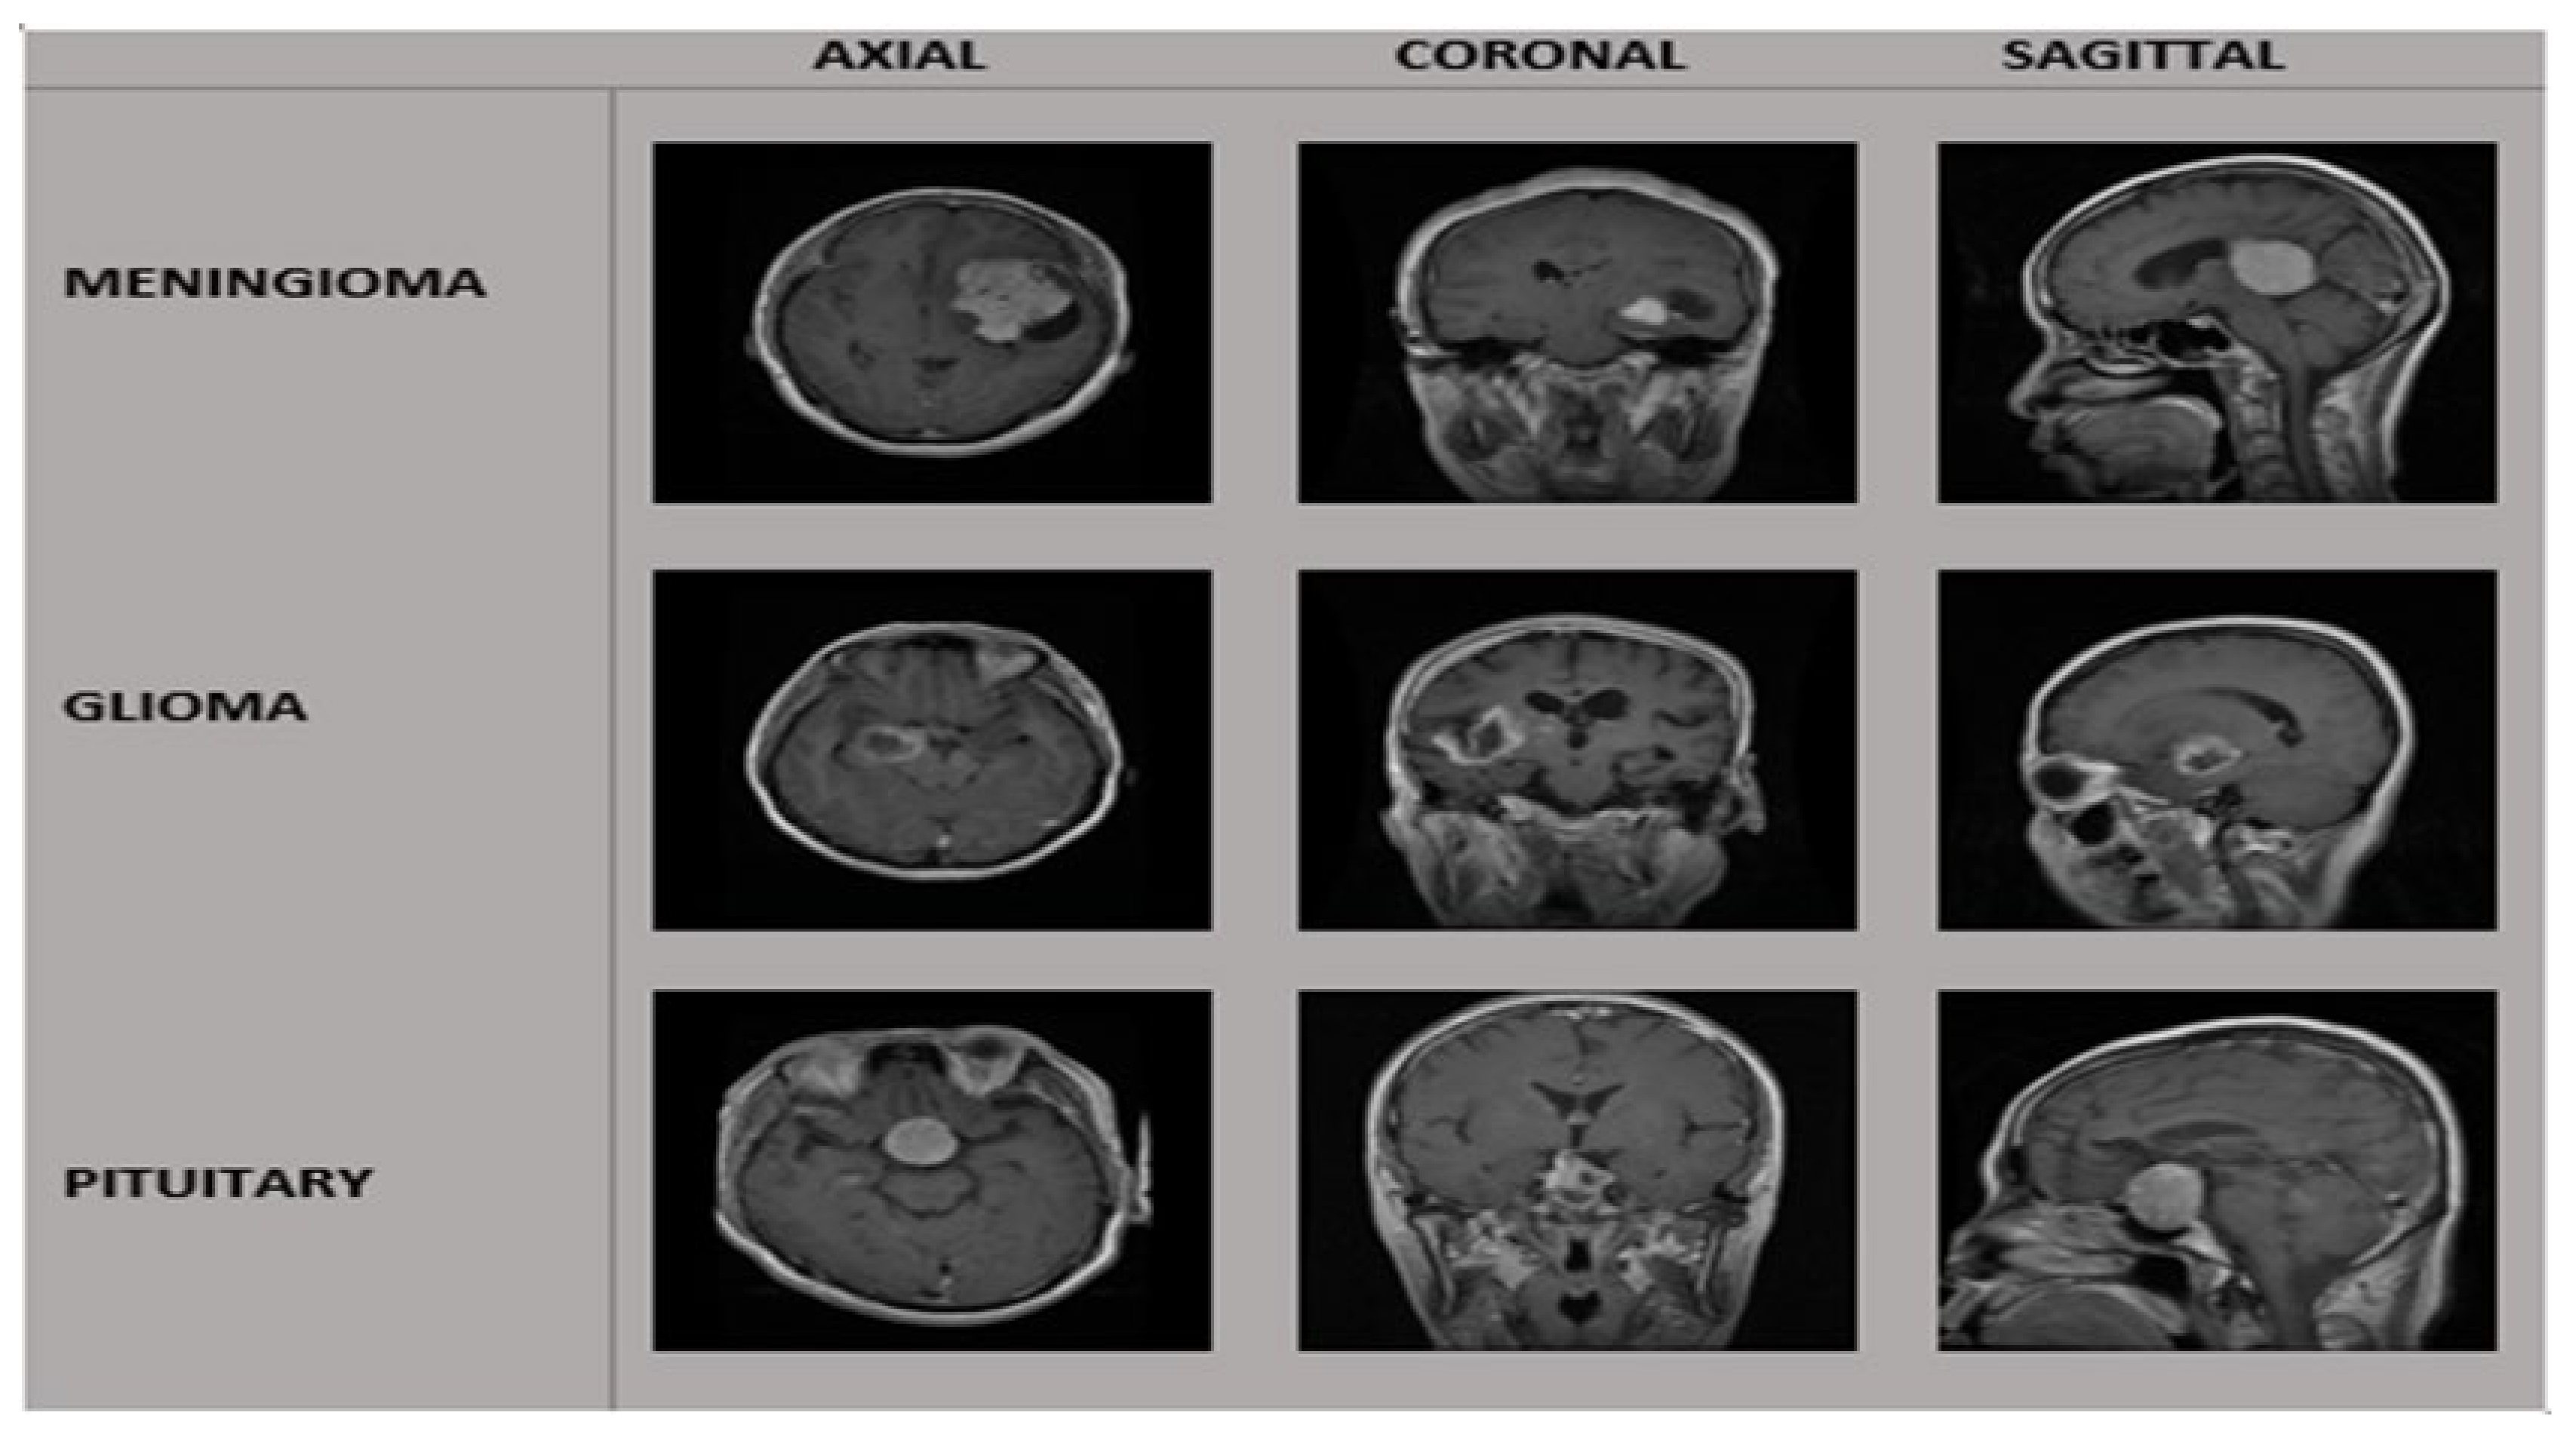

| Tumor Class | Patients | Images | View of MRI. | No. of MRI. Images |

|---|---|---|---|---|

| Meningioma | 82 | 708 | A * | 209 |

| C * | 268 | |||

| S * | 231 | |||

| Pituitary | 62 | 930 | A * | 291 |

| C * | 319 | |||

| S * | 320 | |||

| Glioma | 89 | 1426 | A * | 494 |

| C * | 437 | |||

| S * | 495 | |||

| Total | 233 | 3064 | 3064 |